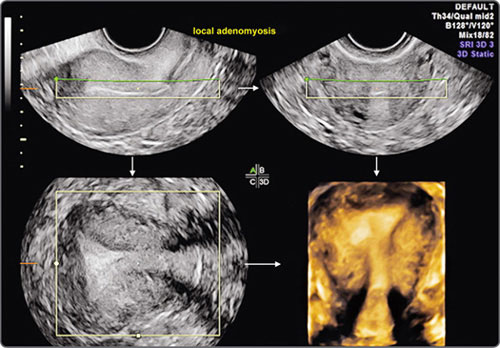

Images may then be rendered by various algorithms which rely on the difference between acoustic impedances at tissue interfaces and have been variably named by various manufacturers. In conventional ultrasound, the endometrium is visualized as a variably thick, linear or ovoid structure in longitudinal, transverse and oblique plane. The shape of the cavity is difficult to assess, as is the coronal plane. With 3D, the entire extent of the endometrium can be shown, including the corpus, fundus, cervix and cornual areas.8 Coronal, sagittal and transverse planes can be simultaneously displayed to permit more exhaustive viewing (Fig. 17).

The images may be automatically zoomed in or out. Once acquired, the volume data can be reviewed by first rotating the planes to obtain standard anatomic orientations and then scrolling through the entire data to locate and characterize lesions, both focal and diffuse. Multiplanar orthogonal viewing offers virtually unlimited numbers of planes, and time constraints should not impede the endeavor to obtain information. In fact, the additional time spent on a 3D gynecologic scan is far less than on 3D obstetric scan because this time is spent not so much on data acquisition but in exploring the data obtained. The time factor would, of course, depend on the complexity of a case and on operator expertise. In experienced hands the exercise takes no more than 3–10 minutes. Once identified in any one plane, the lesion can be marked by a center point, and this center point is automatically displayed in all three orthogonal planes. All or part of the studied volume can be automatically rendered and displayed as a single image or along with the orthogonal planes. The evaluation is enhanced by using volume measurements, niche mode studies, power Doppler studies and a retrospective review of stored data. Unlike obstetric 3D, surface rendering is infrequently required in gynecologic 3D studies except in saline infusion sonohysterography where it often adds diagnostic information. The entire acquired data can be transmitted electronically to obtain second opinions, facilitate remote conferencing with experts, and can be efficiently stored for review and recall.

The sagittal plane is selected for volume measurements and the other two planes for ensuring that the entire pathology is included in the measured area. Surface rendering permits contoural evaluation. Niche mode studies permit a virtual tour of the entire lesion and surrounding tissue along with evaluation of vascular morphology. 3D power Doppler permits an unsurpassed view of vascularity and permits quantification of neovascularization. 3D saline infusion sonohysterography enhances the sensitivity in select situations. Real-time 3D (4D) is useful in saline infusion sonohysterography for storing data sets, excluding the need for re-instillation, permitting multiplanar analysis and allowing magnification of stored data during re-evaluation.

Fig. 17: 3D multiplanar view of an uterus showing longitudinal plane (upper left), transverse plane (upper right), coronal plane (lower left) and rendered view of transverse plane (lower right)